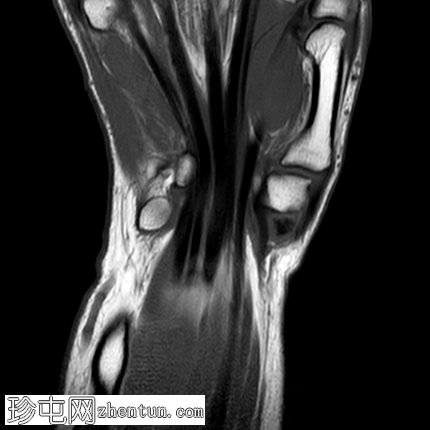

MRI

矢状位

T1加权像

冠状位

PD脂肪抑制像

冠状位PD脂肪抑制像

轴位

轴位PD脂肪抑制像

桡掌侧舟状骨-大多角骨韧带低信号,符合钙化灶,周围伴软组织水肿和舟月关节积液。

本病例为一名既往

的女性,在进行日常家务后,突然出现腕部疼痛和鱼际隆起处肿胀,

影像

学和临床表现均符合急性钙化性关节周围炎的典型特征。